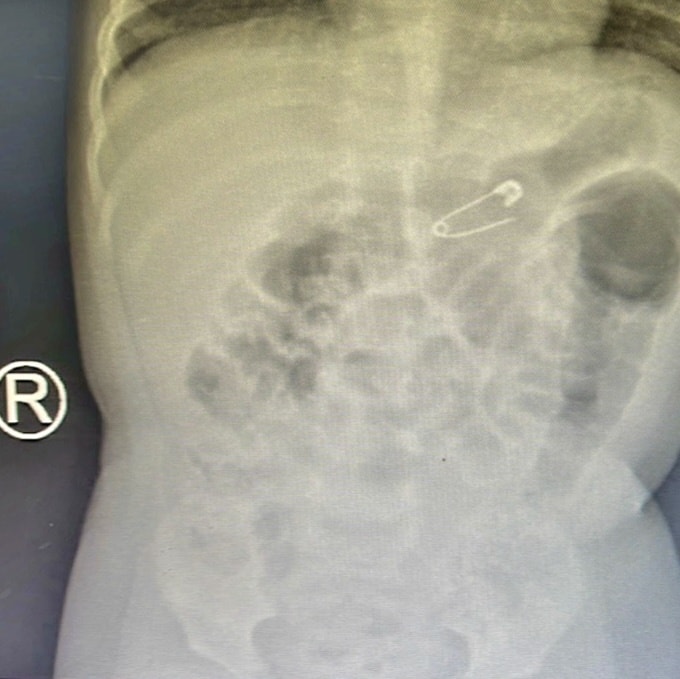

Kết quả chụp X-quang ngực thẳng nghiêng phát hiện dị vật hình kim băng 1,5 x 1 cm, mắc tại khu vực dạ dày của bệnh nhi.

Hình ảnh kim băng bệnh nhi nuốt phải. Ảnh: BVCC